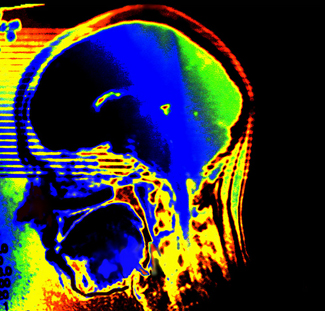

Davant d'un ictus, cal córrer

Un estudi recent dirigit per investigadors de l'Hospital Universitari "Germans Trials i Pujol", adscrit a la UAB, sobre el funcionament del sistema d'atenció mèdica Codi Ictus, implantat fa quatre anys al Barcelonès nord i al Maresme, ha demostrat la seva eficàcia en la rapidesa en...

Codi Ictus. Foto Flickr